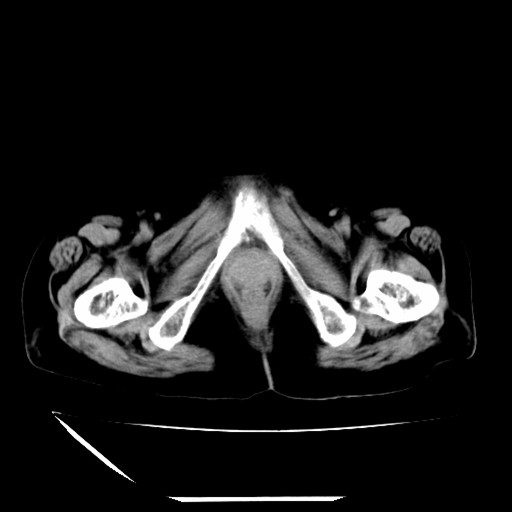

标题: CT16840:女-63岁,下腹部疼痛,

补充资料:血象是13.5,临床拟诊阑尾炎

本人诊断是右肾周围炎,阑尾炎,盆腔少许积液!

诊断右肾周围炎是因为我图像没有发完,诊断阑尾炎是因为相当于阑尾区连续两个层面可以看到增粗的阑尾显影。

支持阑尾炎!局部腹膜增厚,脂肪密度增高。应该手术治疗。